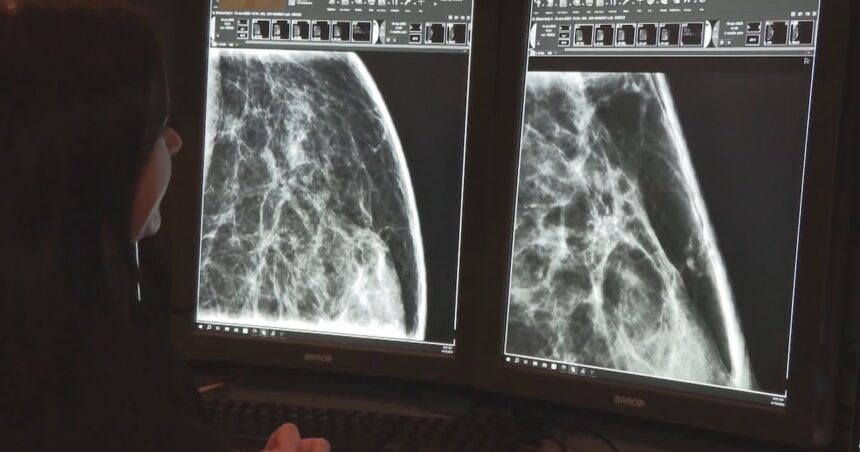

Au service d’urgence de l’Hôpital Memorial de Surrey, le Dr James Wong nous montre leur nouveau système d’aide au diagnostic. Un patient de 67 ans souffrant de douleurs thoraciques vient d’arriver. Pendant que Wong l’examine, l’IA passe en revue les antécédents du patient, ses signes vitaux et les résultats de l’ECG, puis suggère trois diagnostics possibles classés par probabilité.

« Ce n’est pas elle qui prend les décisions, » souligne Wong. « Mais elle aide à s’assurer que je ne manque rien d’essentiel quand nous sommes débordés. Le mois dernier, elle a signalé une dissection aortique rare qui aurait pu être initialement diagnostiquée comme un simple reflux gastrique pendant notre heure la plus chargée. »

Selon une étude récente du Centre d’innovation en santé de la C.-B., les cliniques utilisant ces assistants IA ont réduit les retards de diagnostic de 31 % et le temps consacré à la documentation administrative de près de 40 %. Il ne s’agit pas seulement de mesures d’efficacité, mais de précieuses minutes rendues aux soins des patients.

Les applications les plus prometteuses se trouvent peut-être dans les soins préventifs. Au Centre de santé communautaire d’Edmonds à Burnaby, un système d’IA examine les dossiers des patients pendant la nuit, identifiant ceux qui doivent passer des dépistages de cancer, des vaccinations ou des suivis pour maladies chroniques.

« Il a repéré 18 patients qui étaient passés entre les mailles du filet pour le dépistage du cancer du côlon dès notre premier mois, » indique le Dr Farhad Mehdipour, directeur médical de la clinique. « Deux avaient un cancer à un stade précoce. Ce sont potentiellement deux vies sauvées parce qu’un algorithme a remarqué ce que nous avions manqué pendant nos journées mouvementées. »